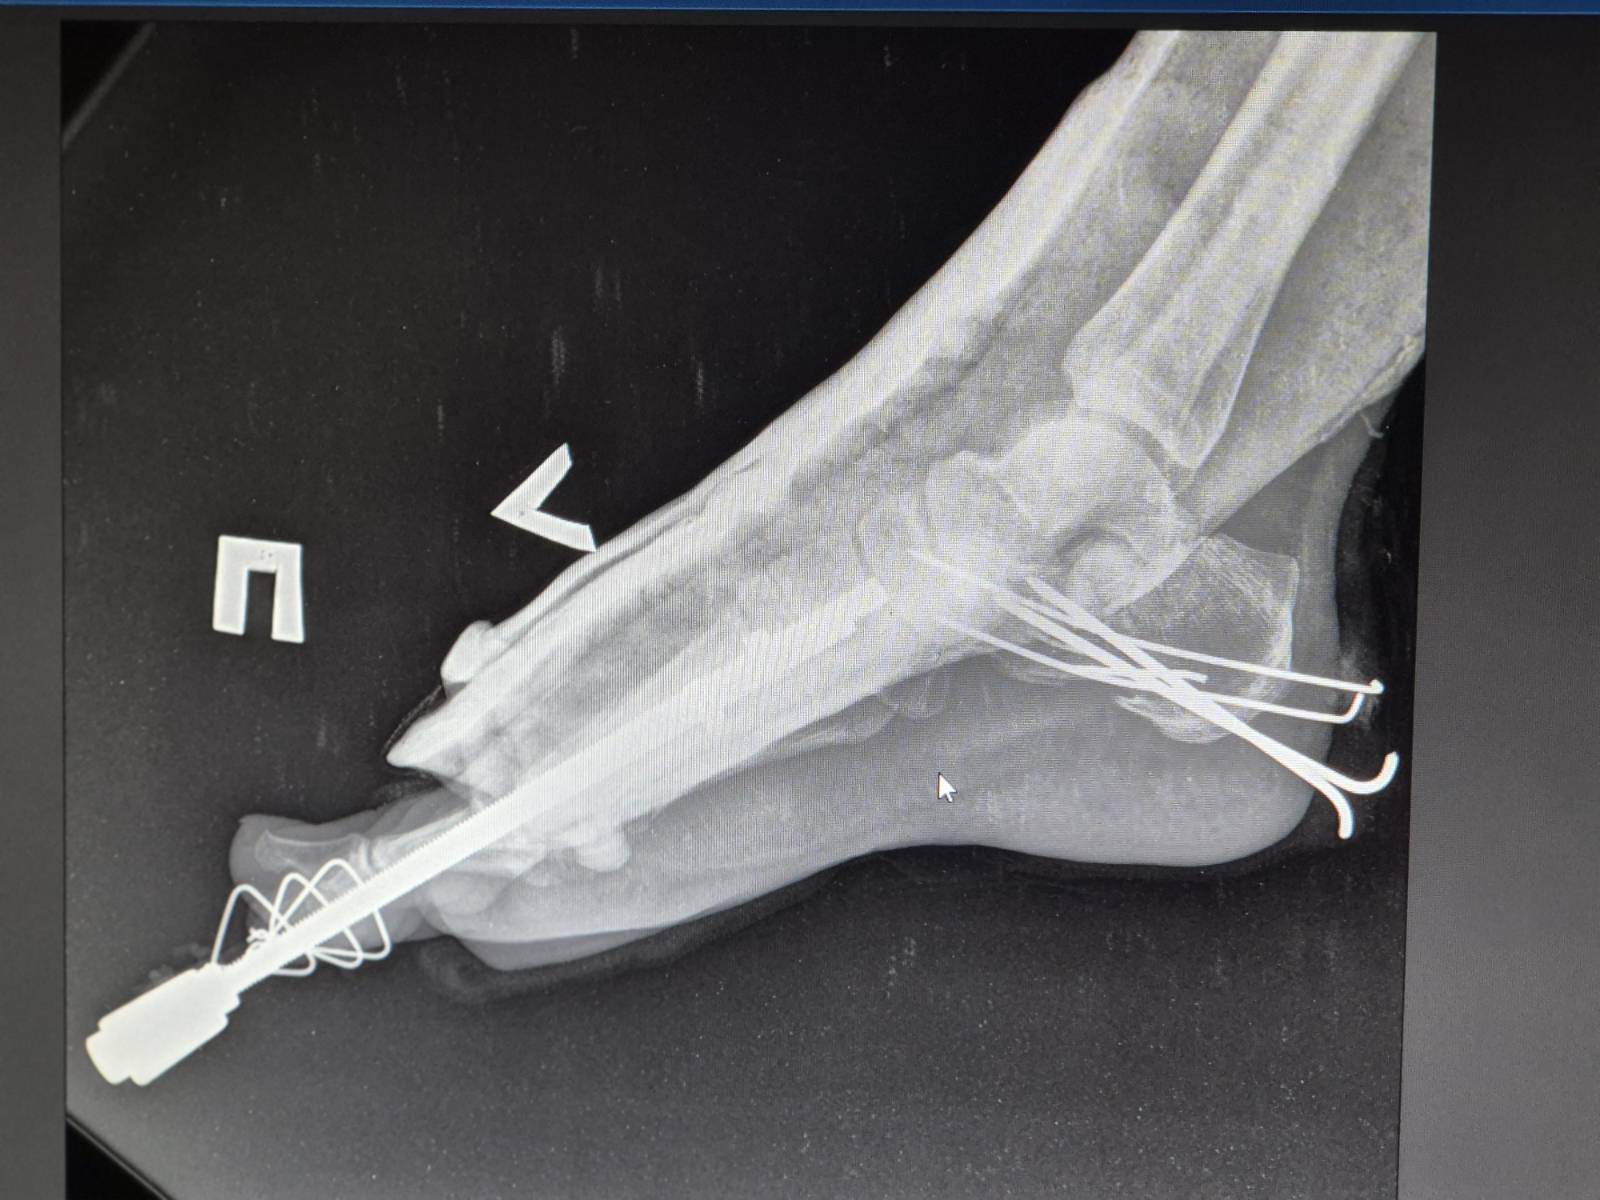

“One of the patients is a female medical worker who was returning home from her shift when the drone struck the bus,” says Olha Severyn, MSF anesthesiologist at the hospital in Kherson. “She suffered severe injuries to her legs and feet. We provided anesthesia and performed surgery.” Another patient arrived with a serious leg fracture and significant blood loss and received timely treatment. Both women are currently in stable condition.

Patients told MSF staff that the drone dropped explosives that detonated under the vehicle, causing many people to suffer injuries to their lower limbs.